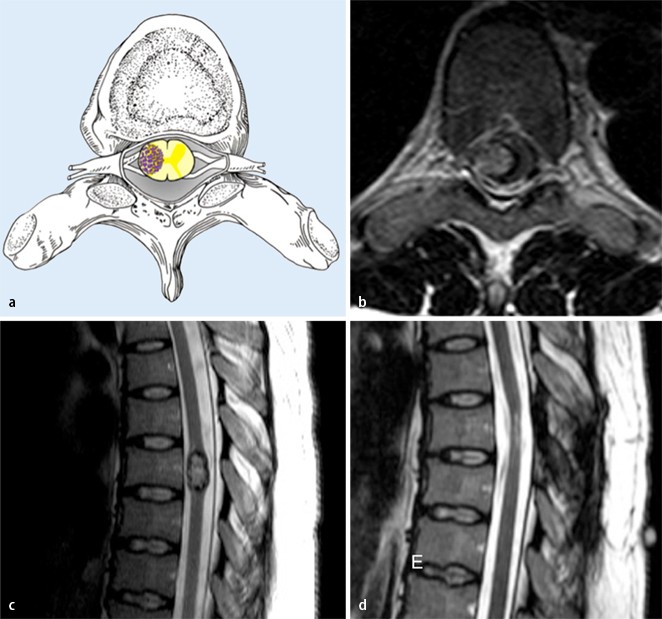

ABCs of the degenerative spine Insights into Imaging Full Text